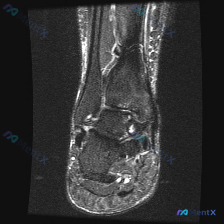

踝关节MRI被怀疑软骨异常?看看这份影像分析怎么说

拿到这份踝关节冠状位T2序列MRI,一开始问题问的是有没有软骨异常,我整理了完整读片和分析思路,大家一起看看。

这是踝关节冠状位T2加权MRI,我们逐层梳理所有结构的表现:

- 骨性结构:胫骨、腓骨远端和距骨形态完整,没有明显骨折线,骨髓信号整体尚可,但距骨内部和踝关节周围部分区域信号不均匀,不能排除轻微水肿或退变

- 关节软骨与间隙:胫距关节间隙没有狭窄,重点说一下:关节面软骨没有看到明显的局限性缺损或者剥脱,所以最初考虑的「软骨异常」其实没有明确影像支持;不过关节间隙里能看到高信号的关节积液,提示存在炎症或者关节腔内压力改变

- 韧带结构:内侧三角韧带没有看到明显断裂或严重水肿;外踝下方的外侧韧带复合体区域,能看到比较明显的软组织水肿和高信号异常,提示这里有损伤可能

- 肌腱结构:内踝后方肌腱走行正常;外踝后方的腓骨长短肌腱走行区域,能看到明显的液性高信号,也就是腱鞘积液

- 周围软组织:踝关节周围软组织肿胀明显,有弥漫性高信号,符合炎症或者外伤后的水肿反应

这些异常都是T2高信号,符合液体或者炎症水肿的特点,弥漫分布边界不清,更符合急性外伤或者炎症过程。

用一元论来解释的话,急性踝关节外侧扭伤(如果患者有反复扭伤史,也可能是慢性踝关节不稳急性加重) 可以解释所有的影像表现:

- 外踝周围软组织水肿是扭伤后直接的水肿反应

- 腓骨肌腱鞘积液是扭伤伴随的肌腱炎症改变

- 关节积液是创伤后的继发性关节内炎症反应

- 骨髓信号不均可能是伴随的骨挫伤

当前影像没有发现明确的软骨异常,之前的怀疑不符合客观影像表现。